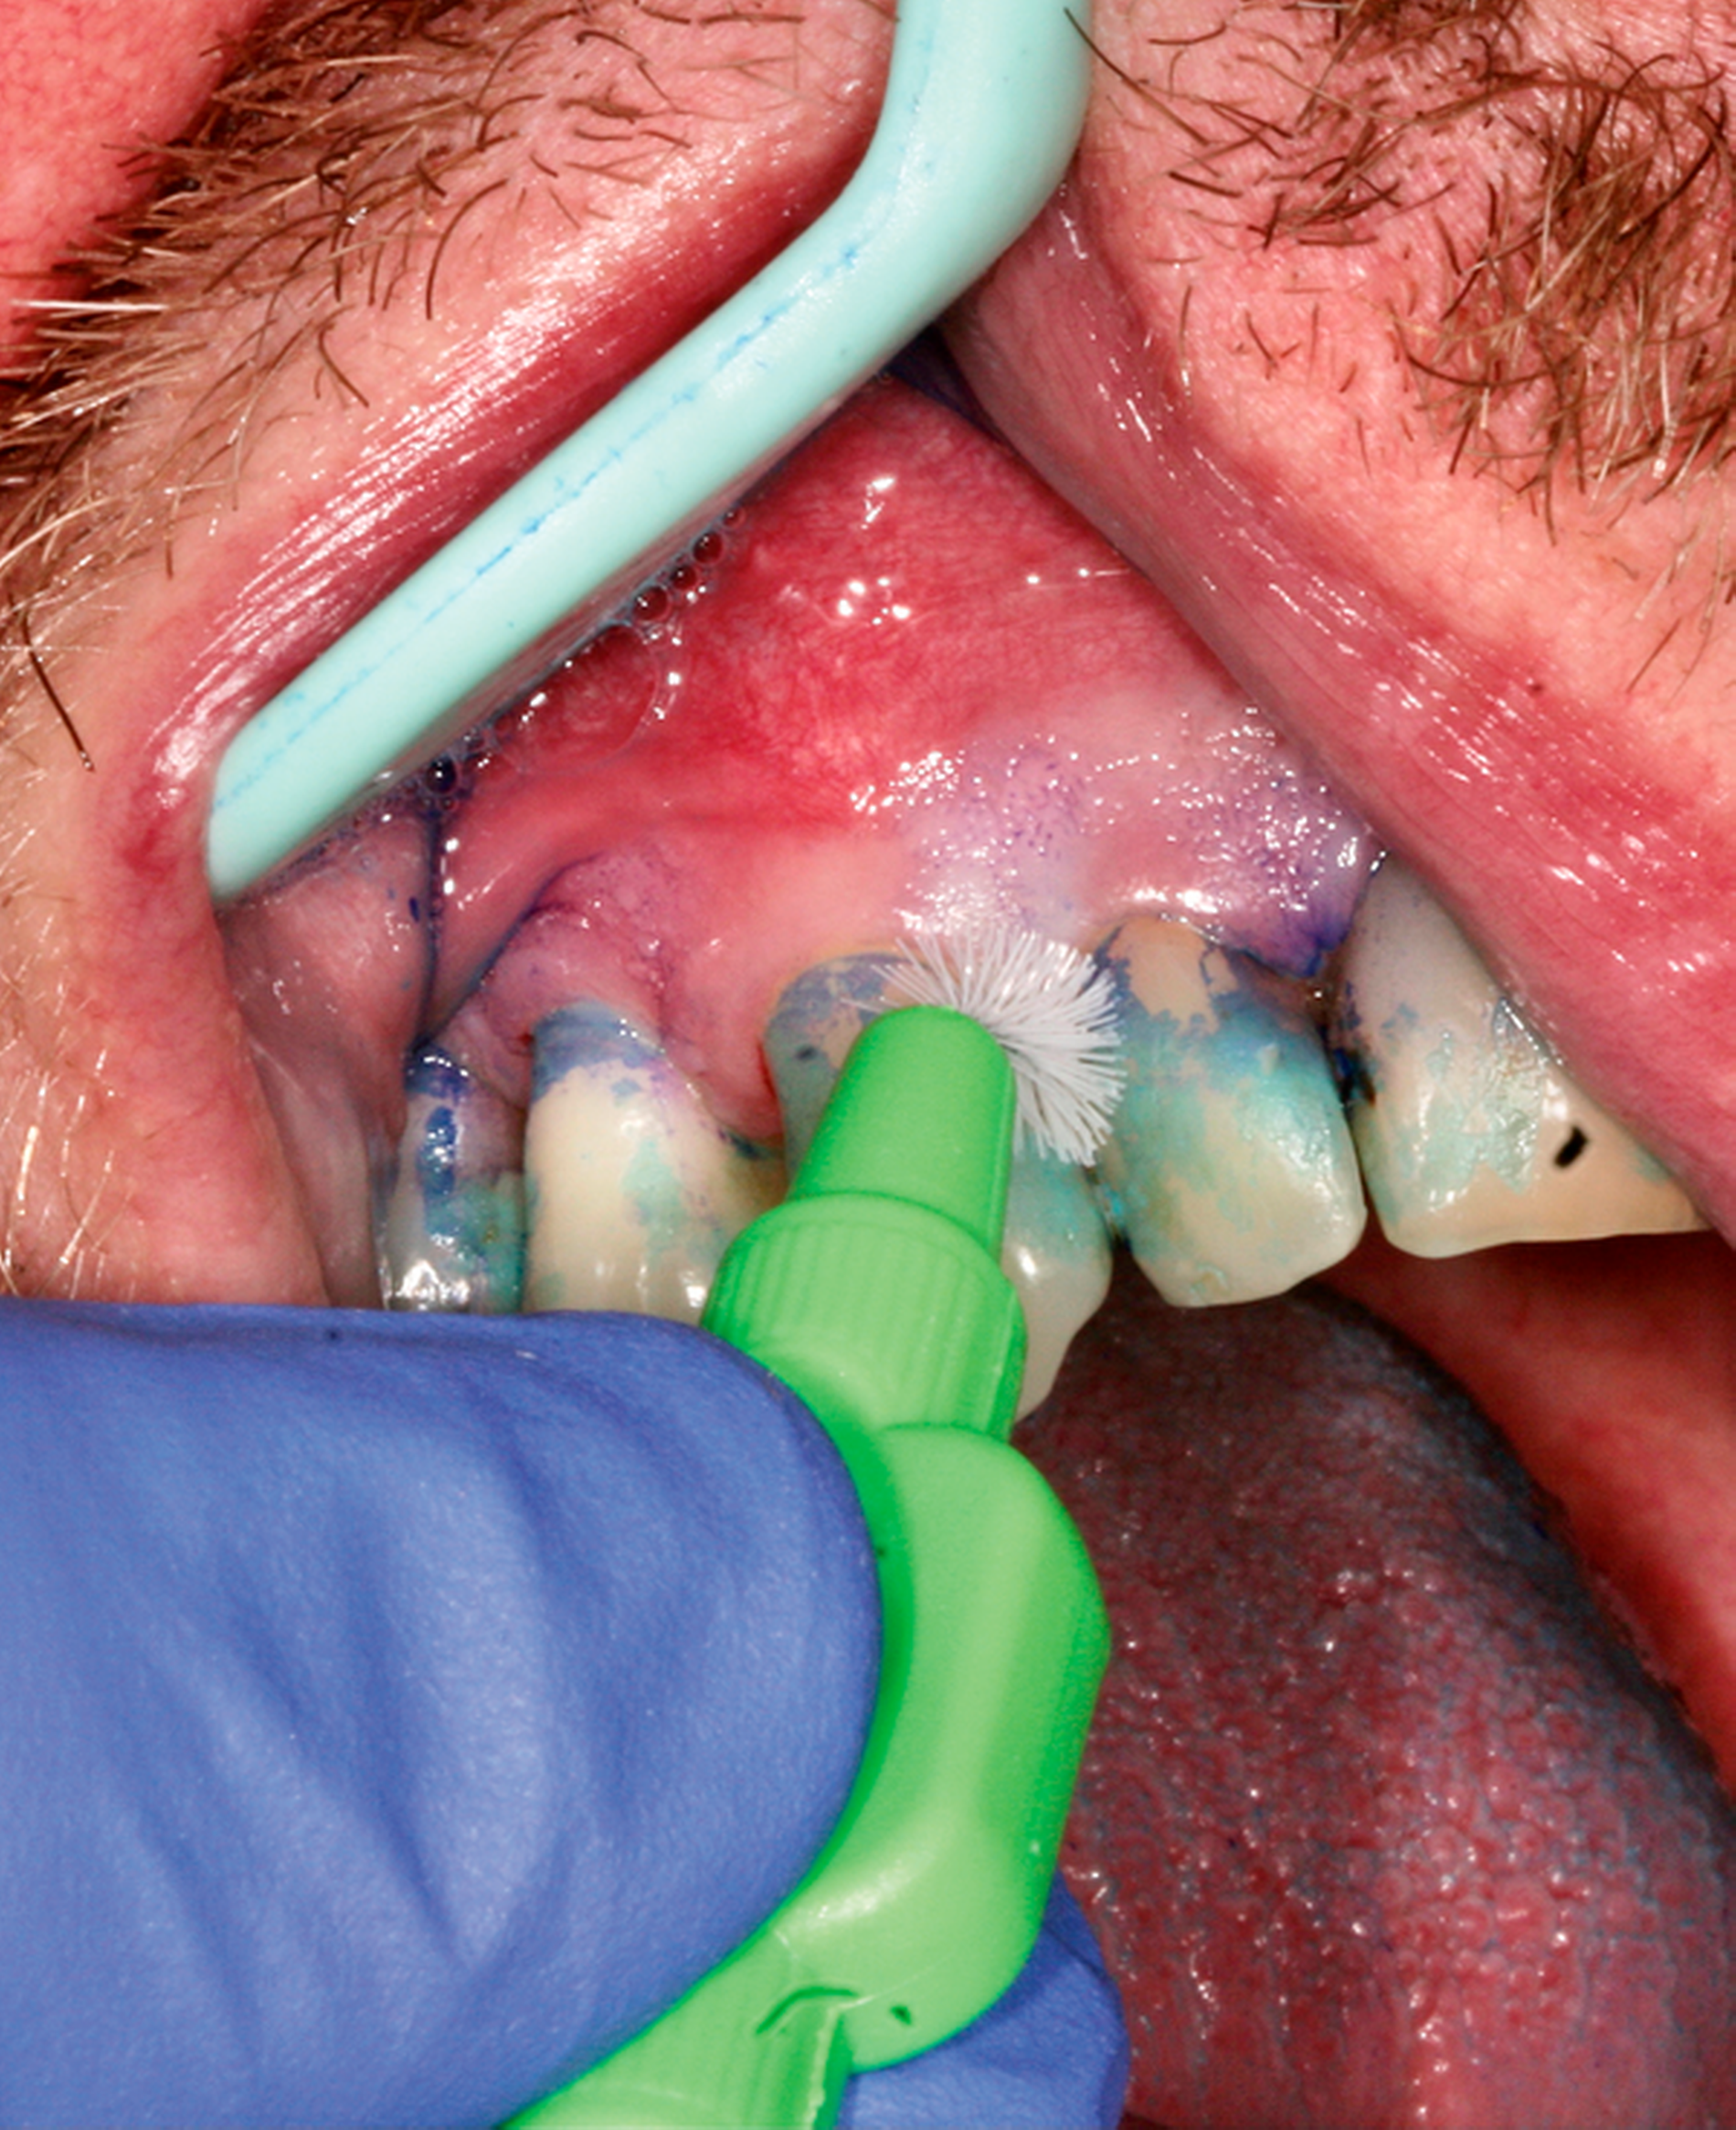

Abb. 2: Professionelle mechanische Plaquereduktion während einer UPT-Sitzung bei einem 50-jährigen Patienten mit reduziertem, aber gesundem Parodont im dritten Jahr nach zweiter Therapiestufe:

Die Empfehlungen für die Intervention in der vierten Stufe sind analog denen aus der ersten Stufe zu formulieren. Die häusliche mechanische Entfernung des Biofilms bildet die Grundlage der Behandlung einer gingivalen Entzündung. Alle Zahnflächen, die der Bildung des oralen Biofilms ausgesetzt sind, müssen effektiv mechanisch gereinigt werden. Einige können aber selbst unter optimalen Bedingungen nicht durch Zahnbürsten erreicht werden. Deshalb ist zum Erhalt der Gesundheit der interproximalen Gingiva die interdentale Reinigung unerlässlich – insbesondere im Rahmen der sekundären Prävention.